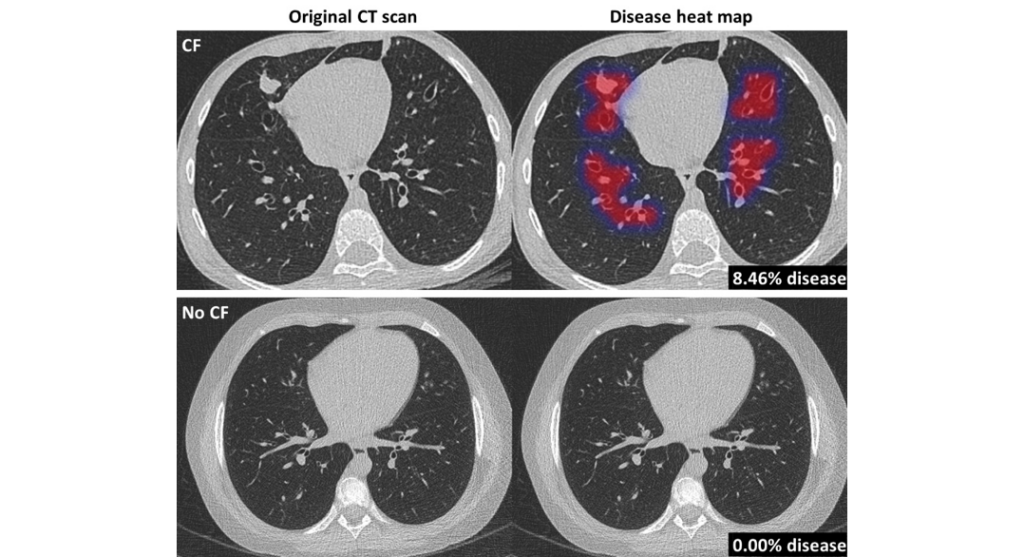

Thirona launches AI software for Cystic Fibrosis

Thirona developed an AI algorithm that revolutionizes cystic fibrosis (CF) care.